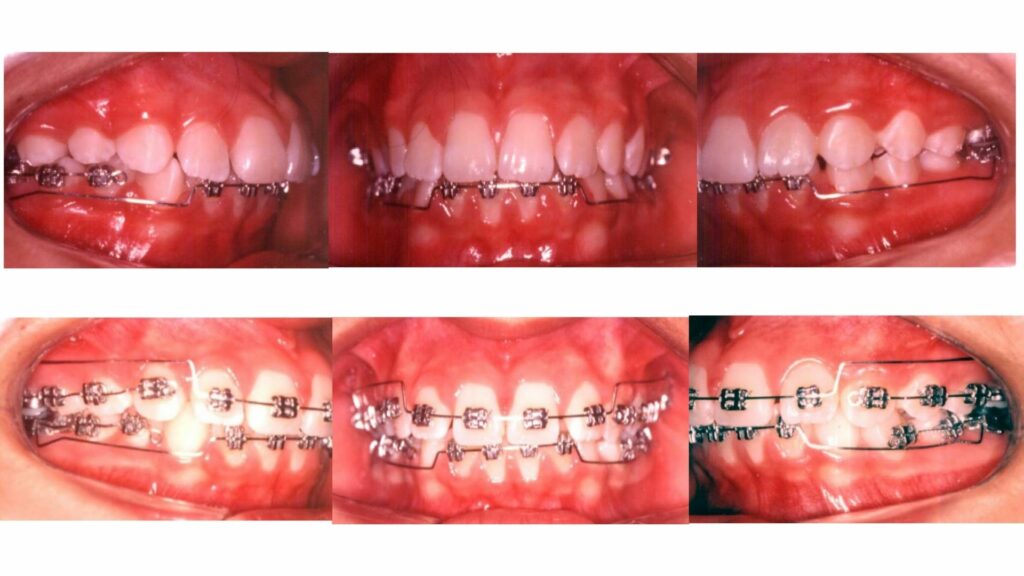

A análise e classificação do tipo facial e da musculatura do paciente é essencial para o planejamento e execução do tratamento. Pacientes com musculatura mais forte são tratados de forma diferente daqueles com musculatura mais suave, garantindo um tratamento mais eficaz e confortável.

Antes de iniciar qualquer tratamento com a técnica Bioprogressiva, três perguntas são essenciais:

Onde estamos? (Diagnóstico)

Para onde vamos? (Planejamento)

Como chegar lá? (Aparelho adequado/mecânica)